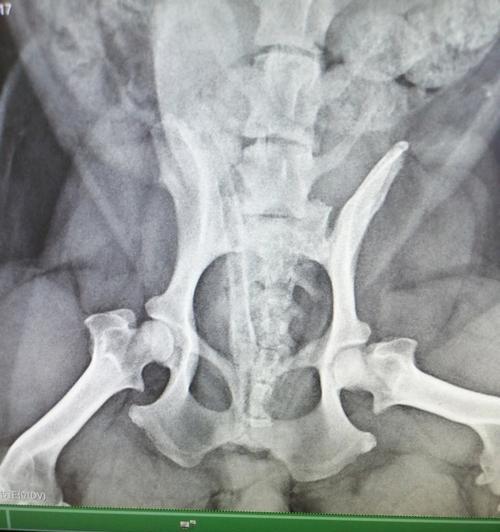

狗狗腿髋坏死严重影响宠物生活质量,早期发现跛行疼痛症状需及时就医。通过合理预防、专业诊断和科学治疗,...